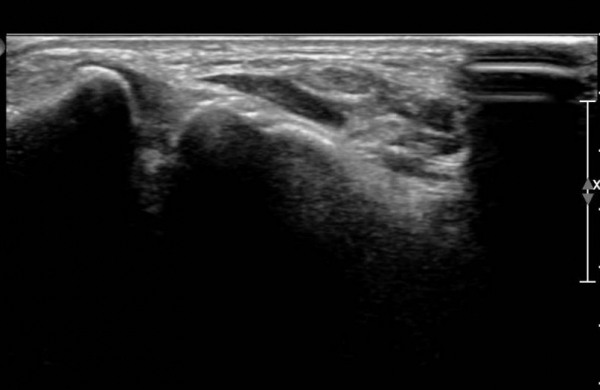

¹Ý´ëÃø  ¾Õ°æ°ñºñ°ñÀδë Á¾´Ü¸é°Ë»ç¿¡¼­  Àδ밡  °í¿¡ÄÚ·Î Á¤»óÀûÀÎ ¸ð½ÀÀ» º¸ÀÓ(»çÁø 7).